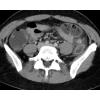

1. Bei der vorliegenden Untersuchung handelt es sich um

- e) eine KM-gestützte CT-Untersuchung

3. Welche der Aussagen zu dem axialen Bild trifft zu?

- a) Verdichtung mit umgebender Fettgewebsimbibierung ventral des Colon descendens

- b) Verdichtung mit umgebender Fettgewebsimbibierung ventral des Colon ascendens

- c) Verdichtung mit umgebender Fettgewebsimbibierung ventral des Colon transversum

- d) Verdichtung mit umgebender Fettgewebsimbibierung ventral der Gallenblase

- e) Kein suspekter Befund, reizlose Darstellung des Colons

5. Welche Diagnose stellen Sie?

- a) Emphysematöse Cholezystitis

- b) Perforierte Diverticulitis mit ausgedehntem Abszess

- c) Perforierte Diverticulitis mit ausgedehnter freier intraabdomineller Luft

- d) Einfache Diverticulitis ohne Perforation

- e) Gedeckt perforierte Diverticulitis